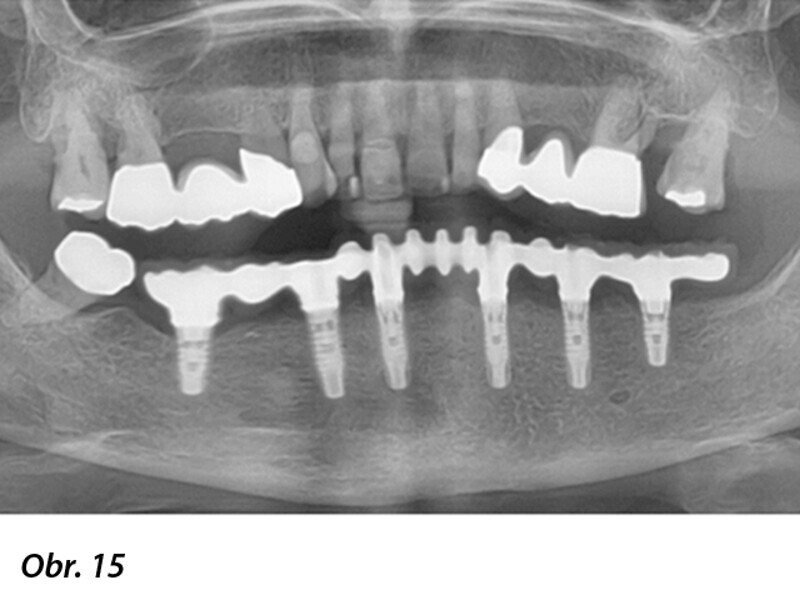

Počítačem asistované, šablonou se řídící okamžité zavedení a zatížení implantátu v dolní čelisti